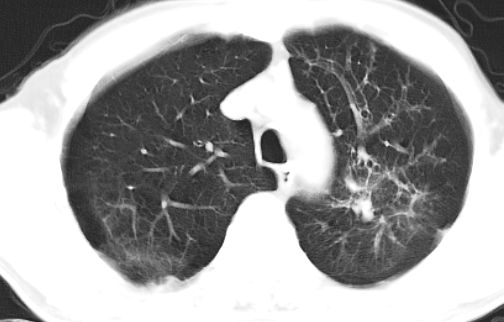

标题: CT10147:男、55岁,咯血10天,有结核病史。 [打印本页]

标题: CT10147:男、55岁,咯血10天,有结核病史。

左上肺见软组织密度肿块影,边缘呈分叶状,可见毛刺,肺门纵隔淋巴结增大,考虑左侧周围型肺癌。左上肺陈旧性结核纤并维化。

左肺分叶状肿块,有毛刺,肺门淋巴结增大.支持左周围型肺癌,肺门淋巴结转移,陈旧性肺结核.

疑点:1 病灶似呈融合成团块,并与肺门区大血管重叠,与上部散在的结节影关系密切。2 周边毛刺多为粗长毛刺。3 左肺门淋巴结肿大,但支气管畅通,未见阻塞。4 纵隔淋巴结不是很大。

双肺上叶结核